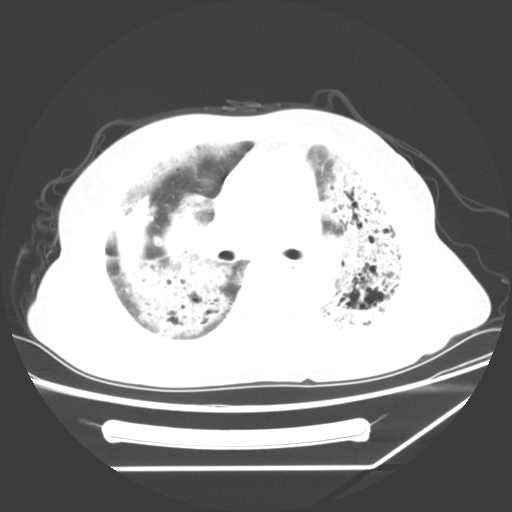

标题: CT25393:病人45岁,咳嗽,吐黄痰带血丝,发热,胸闷月余 [打印本页]

标题: CT25393:病人45岁,咳嗽,吐黄痰带血丝,发热,胸闷月余

1、左肺中央型肺癌并双肺弥漫性转移   2、双肺部感染    3、肺大泡     4、左侧胸腔积液

双侧肺弥漫性病变,可见“空泡征”及“蜂窝征”,考虑肺泡癌可能性大,左侧胸腔积液,考虑胸膜受累可能!

1)不排除肺泡癌可能。2)左侧胸腔积液。